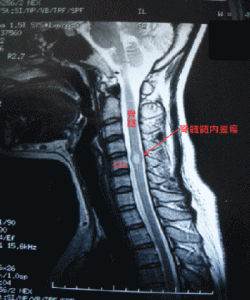

脊髄髄内腫瘍のMRI画像(手術前)

場所:頸髄の5番目(C5)

腫瘍:上衣腫(ependymoma)

大きさ:縦1cm×横1cm

その他:脊髄髄内腫瘍に伴う脊髄空洞症の併発は無し